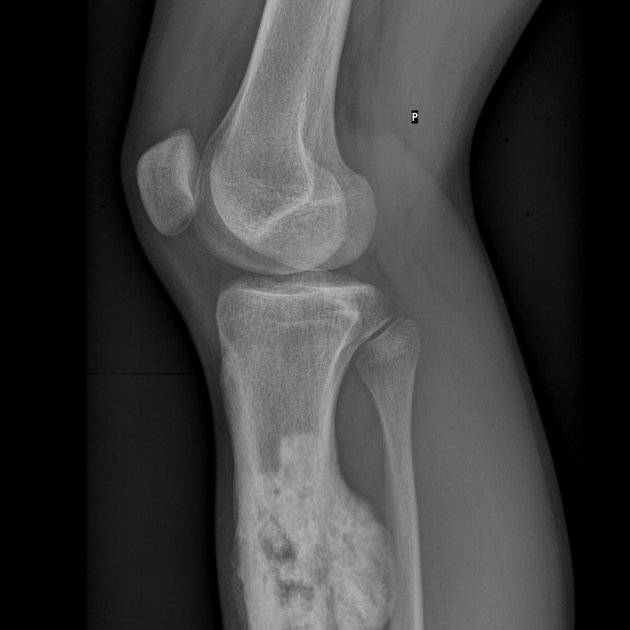

El osteosarcoma es un tipo de cáncer maligno que se produce en el hueso, generalmente en los más largos como la pierna o el brazo, aunque a veces se produce cerca de la rodilla o en la parte superior del brazo. Afecta normalmente a niños y adolescentes, aunque también en los adultos. Suele originar metástasis y, en ocasiones, es muy difícil de tratar.